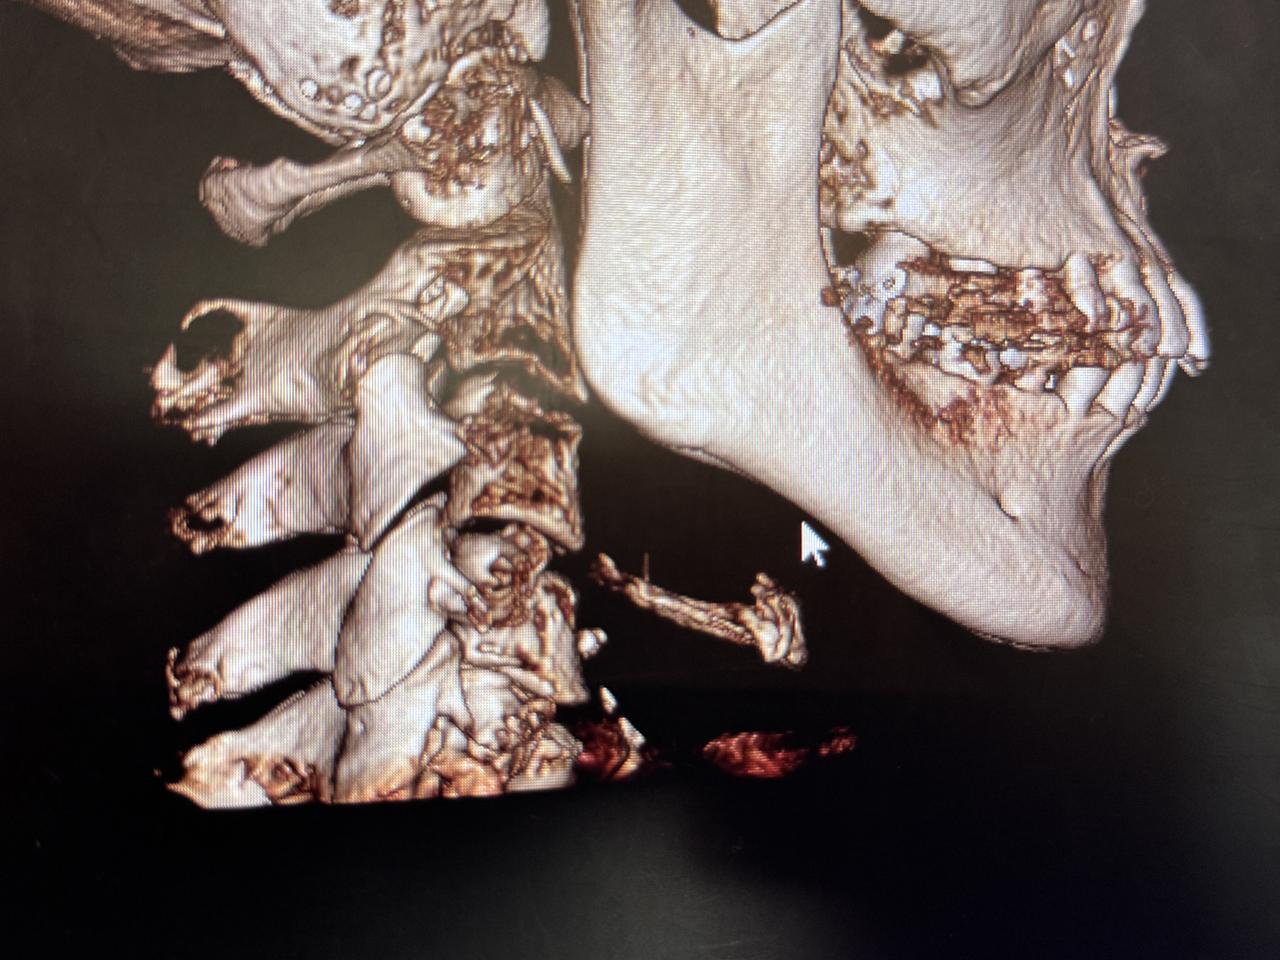

強い奥歯の噛みしめで頭蓋骨にまで影響がでていることが判明

気道が狭くなっているのまでわかります。

歯科用CTは、顎の骨や歯の位置を立体的に捉えることができるため、従来のレントゲンでは見えにくかった細部まで確認することができます。特に「こどもと女性の歯科クリニック」では、かみ合わせの診断に加えて、今回は、以下のような項目もチェックしてくれました。

頭位や頸椎の傾き:

姿勢のクセや左右差が、顎の位置やかみ合わせに影響していることがあります。

呼吸の通り道(気道):

気道が狭くなっていると、口呼吸や睡眠の質に影響する可能性があります。

顎関節の状態:

顎の動きや関節の形状から、食いしばりや顎関節症のリスクを確認できます。

骨格のバランス:

顔の左右差や骨の成長具合など、全身の姿勢にも関係する情報が得られます。

姿勢と口腔の関係は、想像以上に深い

姿勢が悪いと、顎が後方に下がり、かみ合わせがズレたり、気道が狭くなったりすることがあります。その結果、口呼吸になりやすくなったり、歯並びに影響が出たりすることも。歯科用CTは、こうした“見えない原因”を可視化することで、より根本的な治療や予防につなげることができます。歯のことだけでなく、姿勢や呼吸まで見てもらえるなんて驚きでした。